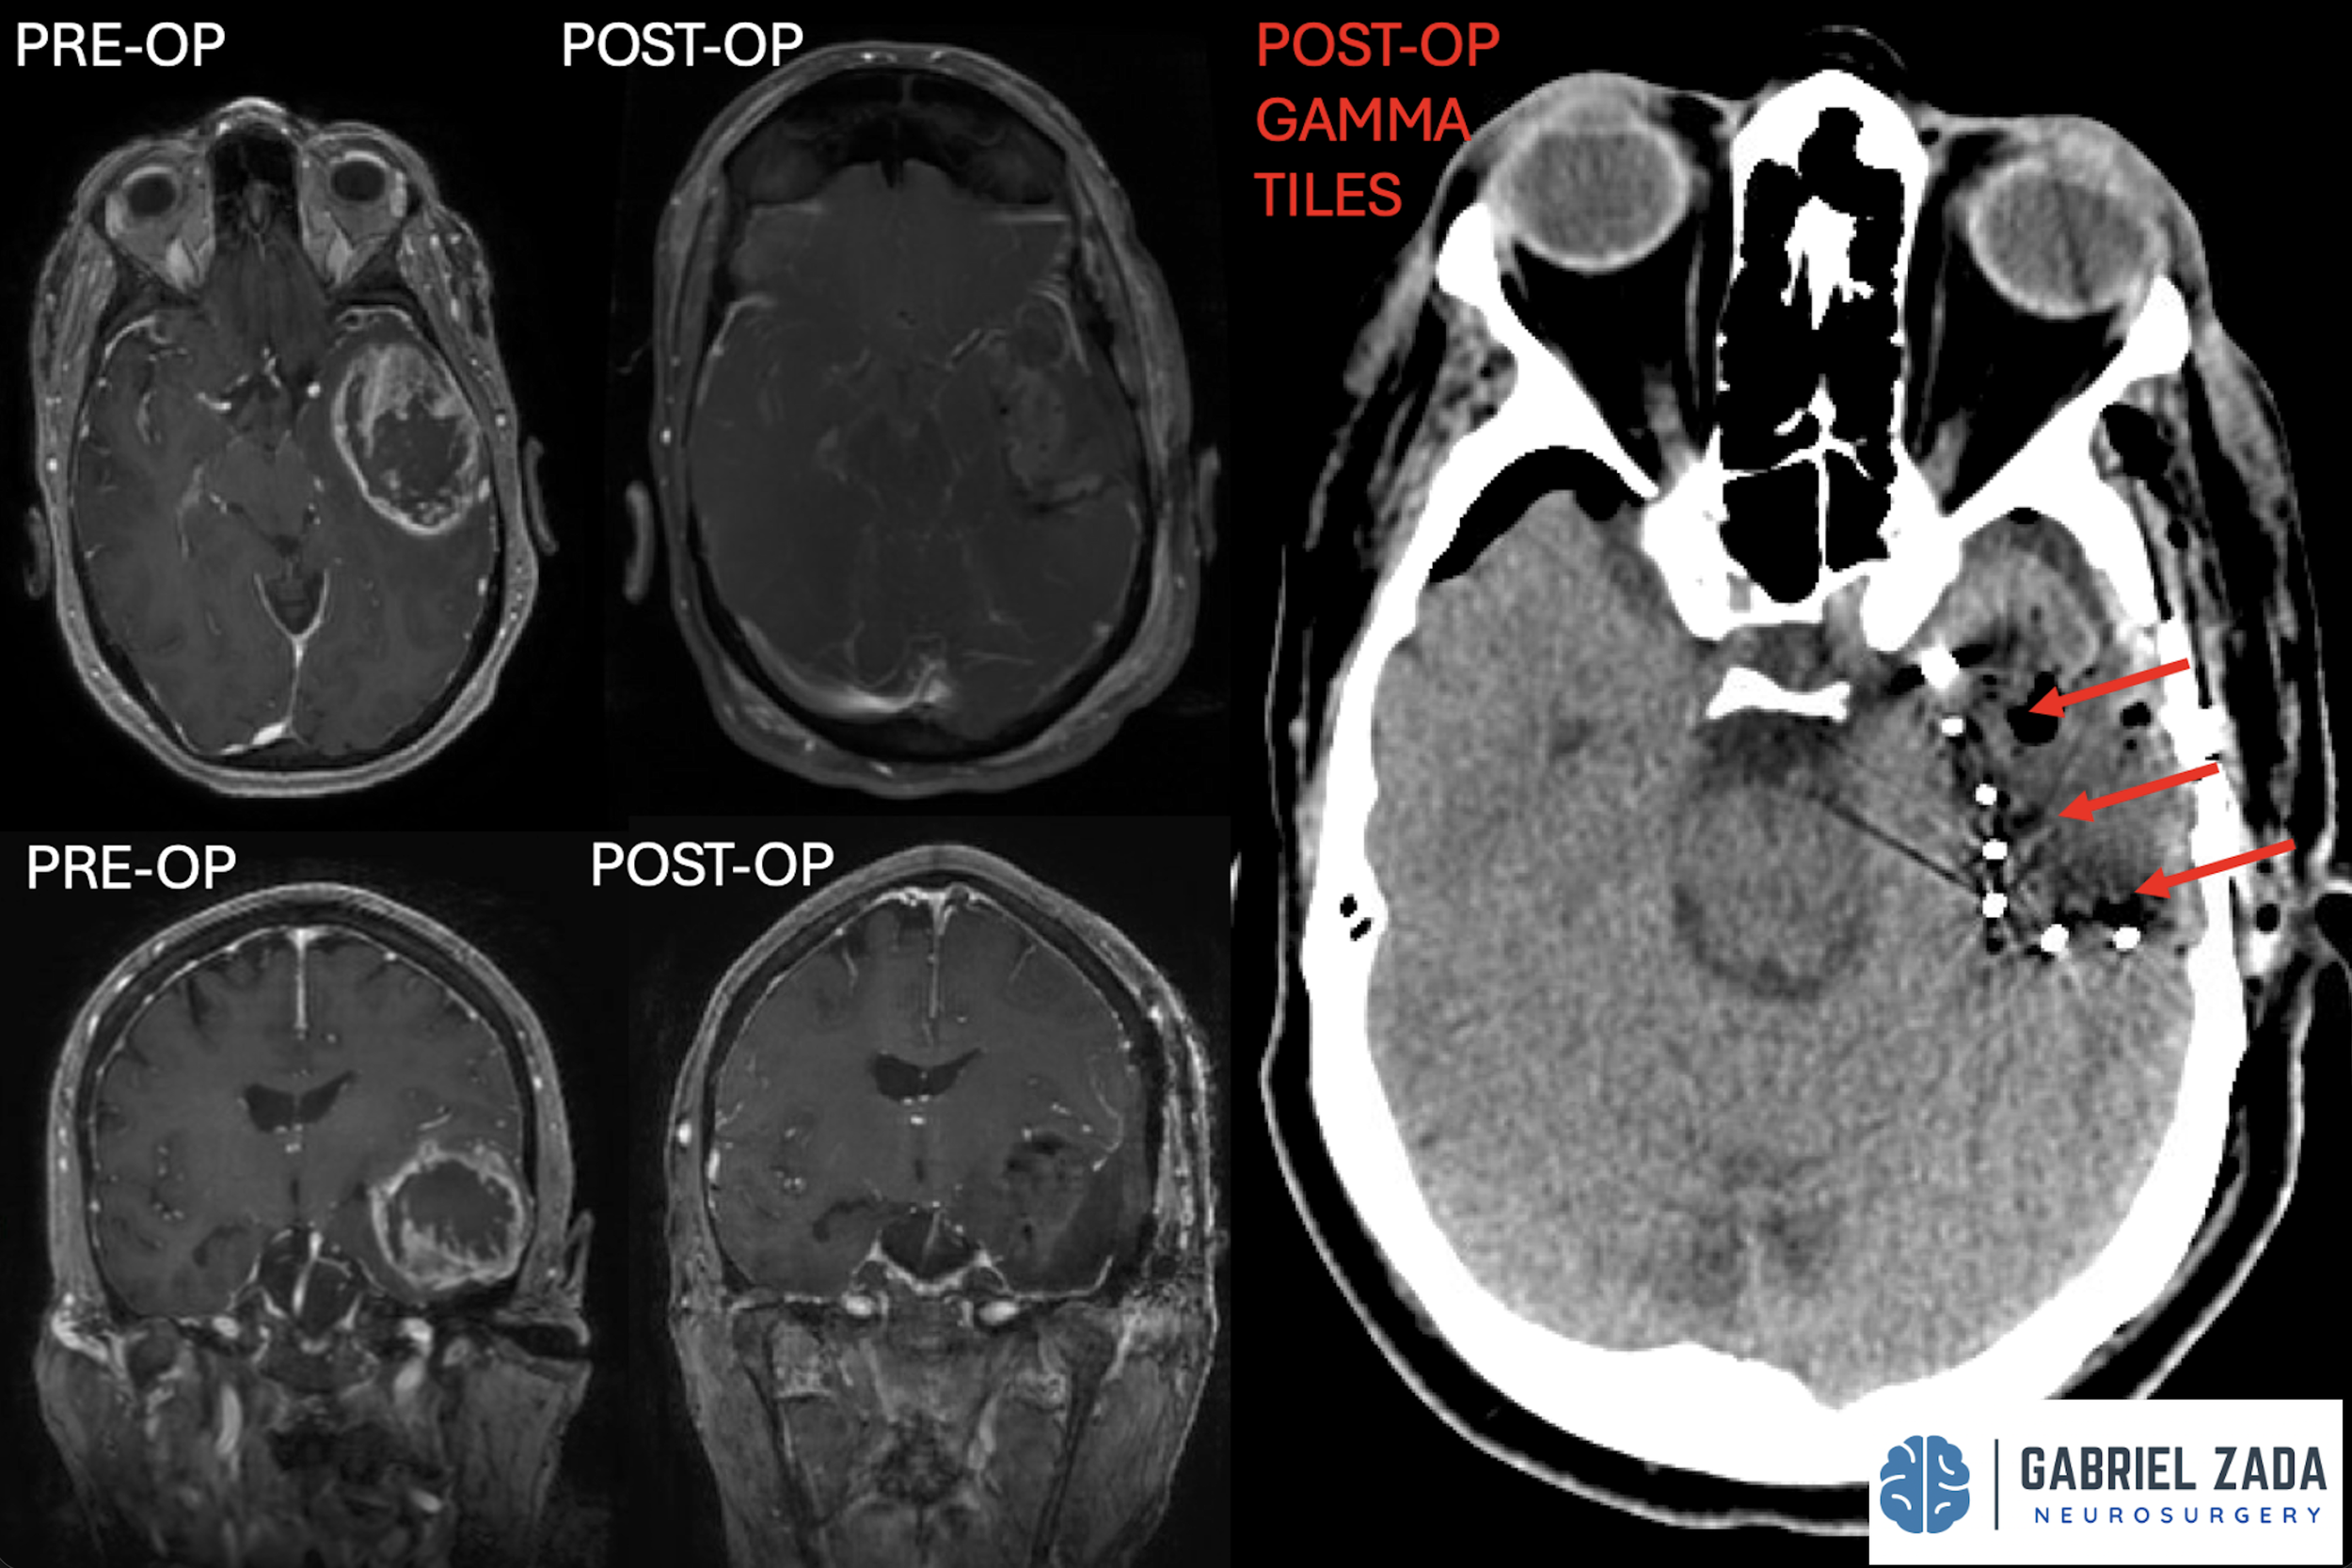

Explore this comprehensive gallery featuring pre‑ and post‑operative imaging of patients with skull‑base tumors treated by Gabriel Zada, MD, MS, FAANS, FACS. These cases highlight Dr. Zada’s expertise in advanced neurosurgical techniques and outcomes.

*Representative cases shown for educational purposes. All images de-identified. Individual results vary.